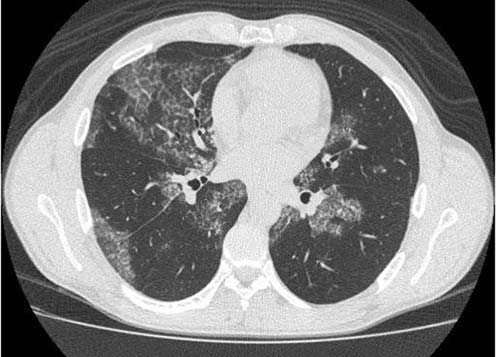

При компьютерной томографии получена картина, позволившая заподозрить альвеолярный протеиноз (рис. 4).

Рис. 4. Фрагменты компьютерной томограммы больного Б.

Выявляются 2-сторонние зоны "матового стекла" с утолщением в них междольковых перегородок, четко отграниченные от интактной легочной паренхимы.

Рис. 10 а, б. Фрагменты компьютерной томограммы больного Б. после про ведения БАЛ.

Уменьшение распространенности и интенсивности зон "матового стекла).

По данным КТВР после проведения БАЛ также выявлена положительная динамика (рис. 10 а, б).

Таким образом, на фоне проведенного бронхоальвеолярного лаважа отмечена положительная динамика по рентгенологическим данным (КТВР), которая также подтверждена данными конфокальной лазерной эндомикроскопии.